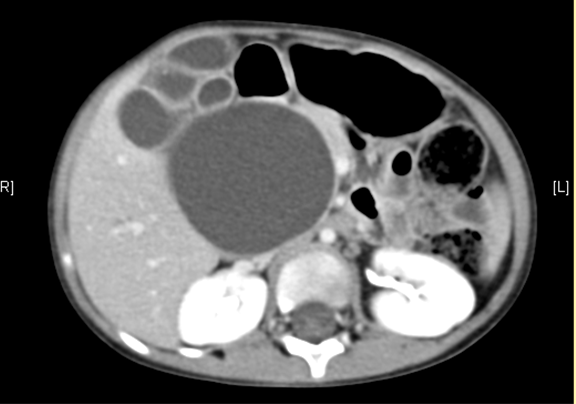

腹部CT 增强:1. 肝内外胆管扩张,考虑胆总管囊肿并胆系扩张可能性大2. 胆囊结石。

将0.625mm双源薄层CT资料的静脉期和动脉期Dicom格式文件导入海信CAS系统。

通过调节窗宽窗位调整CT序号,对肝实质,胆囊,下腔静脉,肿瘤,肝动脉、门静脉及肝静脉等进行三维重建;系统自动计算肝脏体积。

术前CT检查:

动脉期

静脉期

平衡期